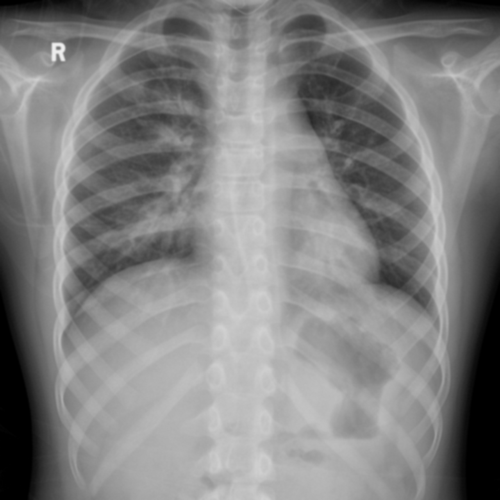

To pre-train a high-performance X-ray foundation model, the first thing we need to do is the collection of large-scale X-ray images. Therefore, a large-scale and high-resolution dataset that contains X-ray medical images is collected for the pre-training. Some representative samples are visualized in Fig. 3.